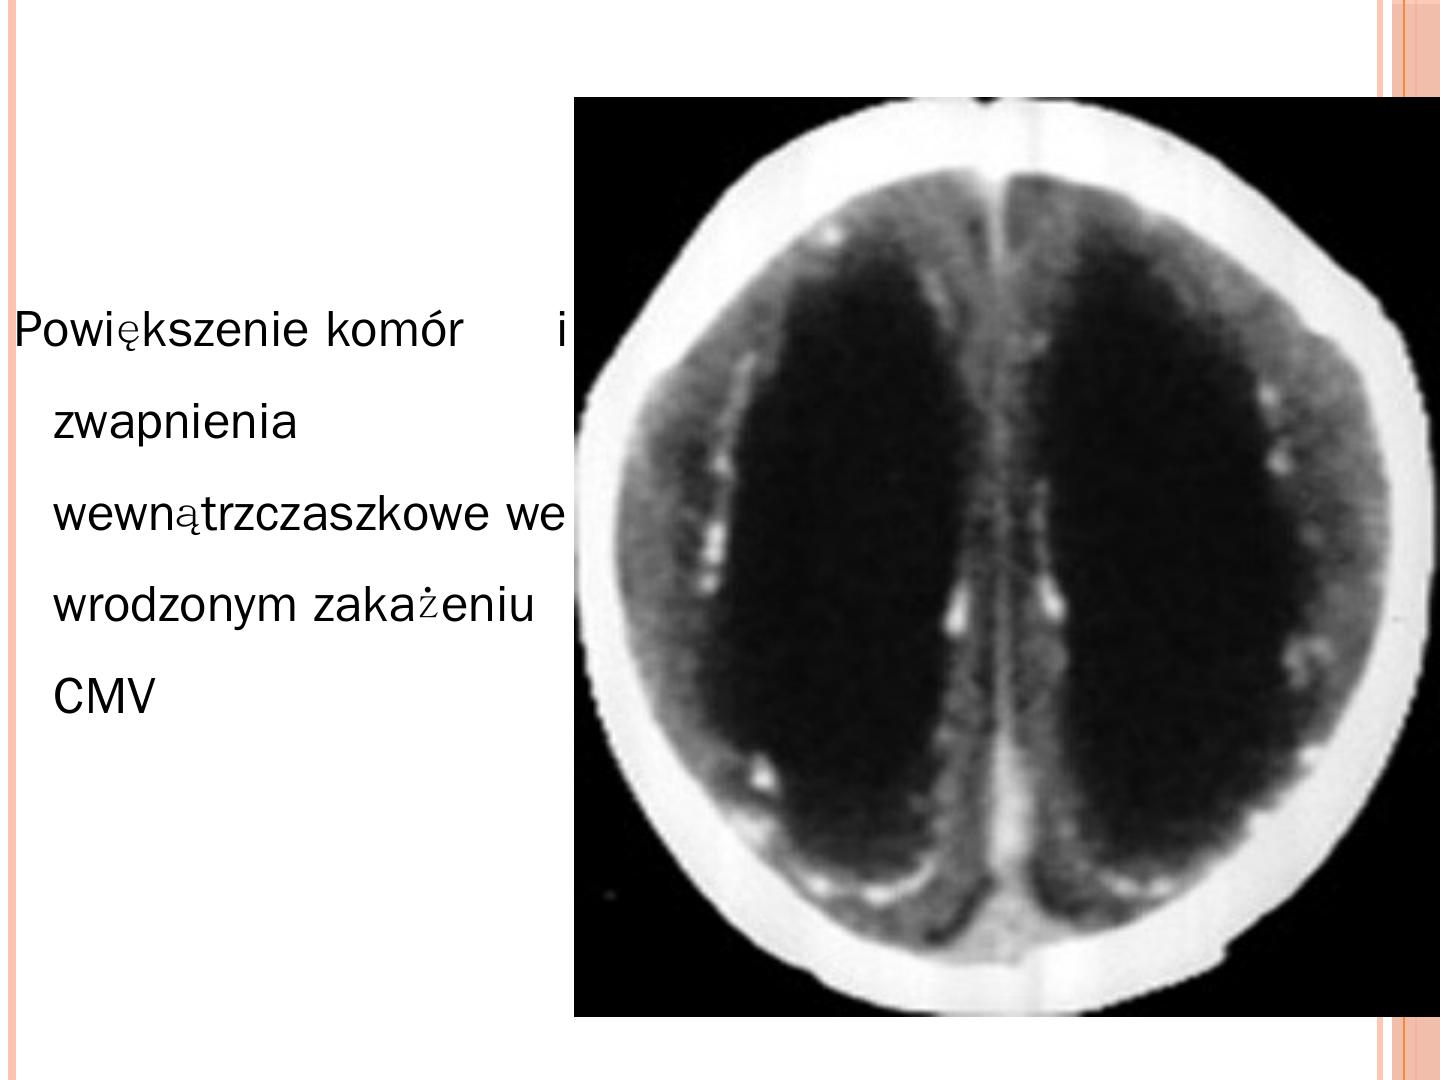

Ewa Majda-Stanisłąwska. Mikroorganizmy powodujące zakażenia wrodzone. TORCH. Toksoplazmoza; Różyczka; Cytomegalia; Herpes simplex wirus typ 2.